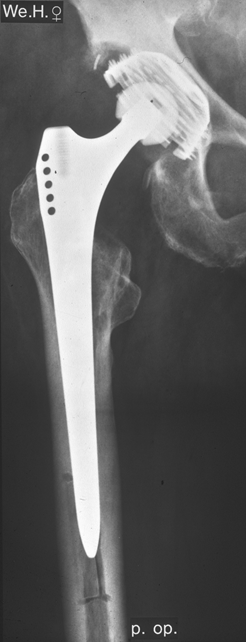

Fallbeispiel

Weiblich 73 Jahre, Zustand nach Implantation einer

zementierten Hüftprothese der rechten Hüfte es findet sich eine massiv gelockerte Hüftpfanne

sowie eine beginnende Schaftlockerung.

Postoperatives Bild

Monitorgezielte Röntgenaufnahme der Bicon-Pfanne, ein

Monat postoperativ. Im oberen Anteil ist die Pfanne

aufgrund des vorhandenen Defektes nicht mit Knochen

bedeckt.